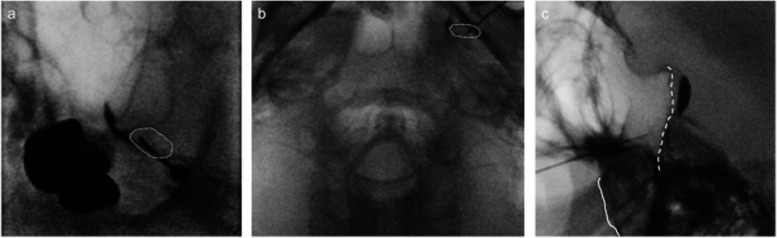

Case presentation: A 49-year-old male with multiple sclerosis exhibited persistent dull pain and paroxysmal electric shock-like pain in his bilateral maxillary molars and mandible. He was diagnosed with trigeminal neuralgia due to multiple sclerosis. Due to severe side effects, it was difficult to achieve adequate pain control with medication alone. By performing low-temperature radiofrequency thermocoagulation and pulsed radiofrequency of the Gasserian ganglion while monitoring masseter muscle contraction, a satisfactory and rapid analgesic effect was obtained without masticatory atonia.